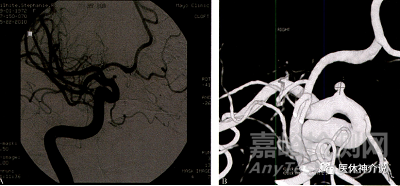

1-小動(dòng)脈瘤

FD治療小動(dòng)脈瘤的有效性與大/巨大動(dòng)脈瘤類(lèi)似,使用單一裝置處理多發(fā)、小型、彼此鄰近的動(dòng)脈瘤時(shí)更具優(yōu)勢(shì)。FD可誘導(dǎo)載瘤動(dòng)脈管腔重建,無(wú)需將微導(dǎo)管額外超選至小動(dòng)脈瘤腔內(nèi),降低了動(dòng)脈瘤的醫(yī)源性破裂風(fēng)險(xiǎn)。

一項(xiàng)中位隨訪期65個(gè)月的多中心隊(duì)列研究納入直徑≤7mm的頸內(nèi)動(dòng)脈眼段動(dòng)脈瘤,完全閉塞率為87%,并發(fā)癥率與傳統(tǒng)血管內(nèi)治療相當(dāng),無(wú)術(shù)中破裂發(fā)生。該研究中86%的患者使用單個(gè)PED治療,17%為多發(fā)動(dòng)脈瘤。

通常認(rèn)為,前循環(huán)小動(dòng)脈瘤的自然病史為良性。風(fēng)險(xiǎn)程度低于同部位的大動(dòng)脈瘤。但是,疾病自然進(jìn)程中的風(fēng)險(xiǎn)必須個(gè)體化分析,并與FD治療的圍手術(shù)期風(fēng)險(xiǎn)相權(quán)衡。